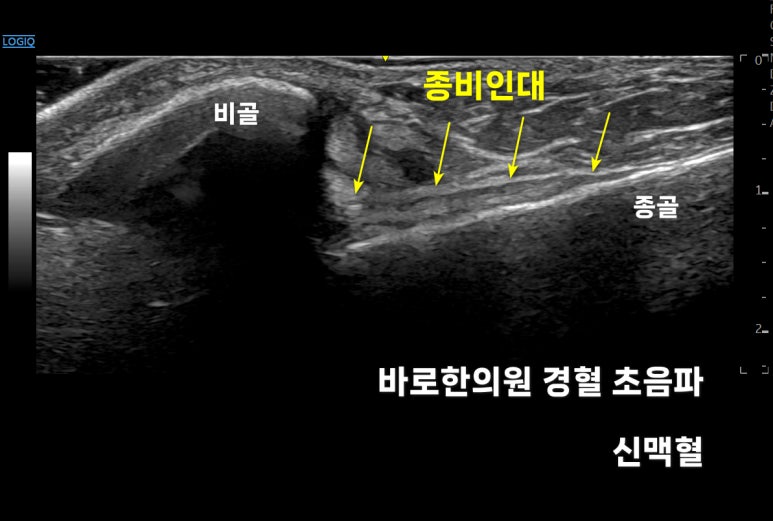

발목 바깥쪽 뒤쪽

신맥혈에서

'종비인대'**를 확인해봐야 합니다.

'종'골과 '비'골을

안정적으로 고정해주는 역할을 하죠.

다행스럽게 이 환자분은

종비인대가 정상적으로 기능하고 있었습니다.